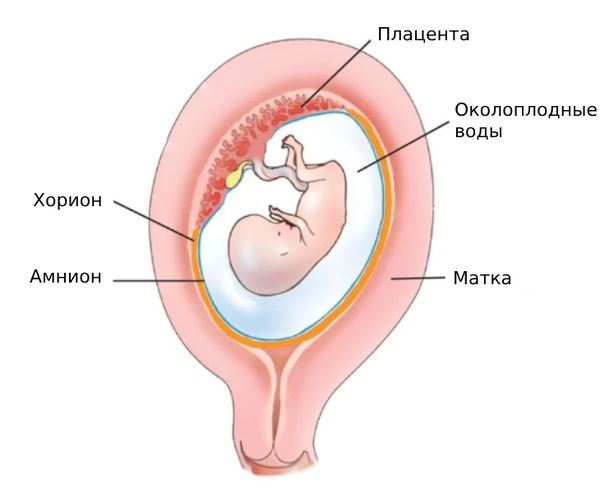

Амнион и Околоплодные Воды: Функции и Роль в Беременности